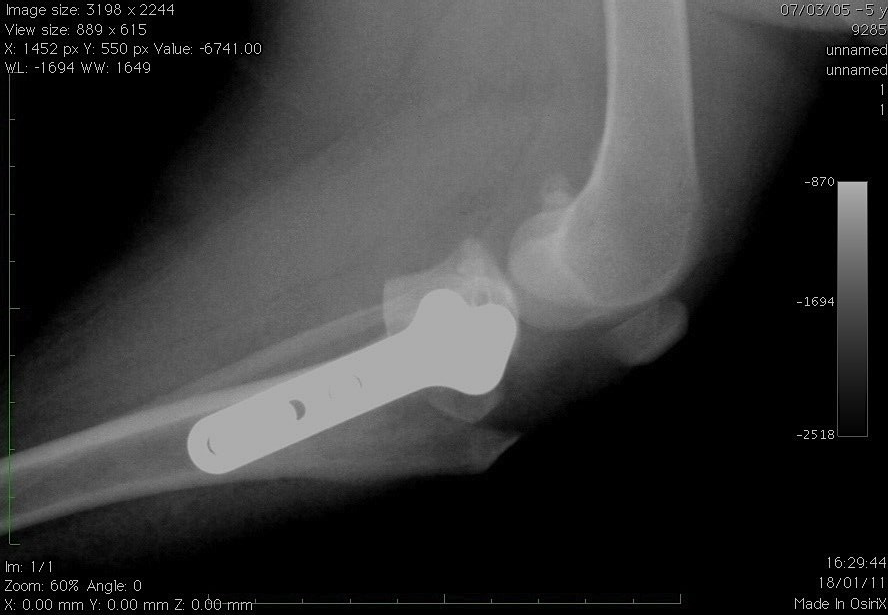

- Les traitement des pathologies du coude ou de l’épaule (dysplasie du coude, ostéochondrite de l’épaule, etc…).